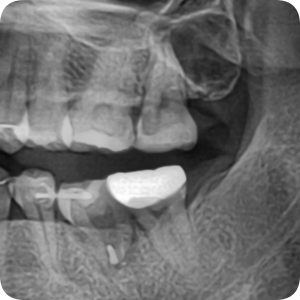

치근절제술로 자연치아 살려서 임플란트 피하기 - 내가 돈 못버는 치과의사가 된 이유

상악 1대구치 잇몸 염증으로 다른 치과에서 발치진단을 받고 온 환자입니다. 제가 어쩌다보니 자연치아 살...